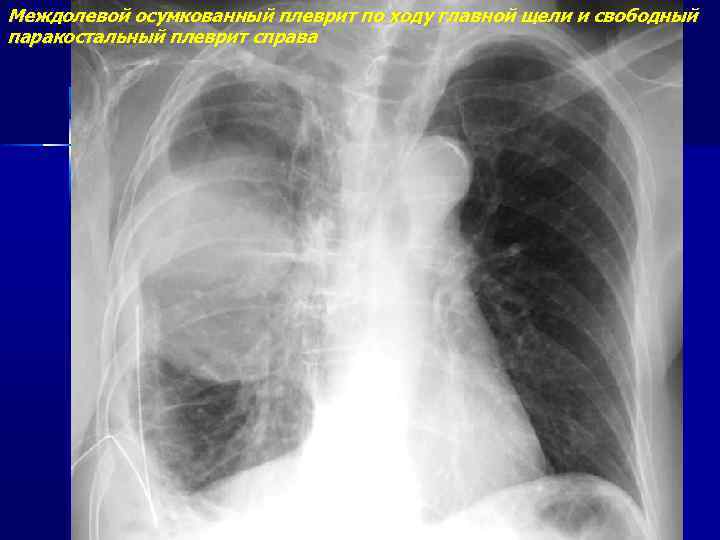

Диагностика плеврального выпота: что нужно знать